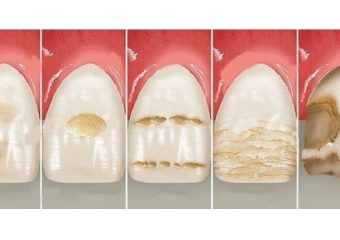

علل و نشانه فرسایش مینای دندان

علل و نشانه فرسایش مینای دندان

فرسایش مینای دندان

درست است که مینای دندان محکم ترین بافت بدن می باشد اما همواره در معرض آسیب ها و فرسایش قرار دارد. این بخش از دندان معمولا با استخوان مقایسه می شود اما در استخوان ها در اثر آسیب یا شکستگی می توان ترمیم خود به خودی سلول ها و بهبود آن را مشاهده کرد در صورتی که در مینای دندان این ویژگی وجود ندارد. در واقع اگر مینای دندان شما آسیب ببیند به صورت طبیعی ترمیم نمی شود و بهبود در اثر فعالیت سلول ها دیده نمی شود زیرا این بخش عاری از سلول می باشد. عوامل متعددی هستند که می توانند به مینای دندان های شما آسیب بزنند.

نشانه های بروز فرسایش

علائم این مشکل بسته به شدت فرسایش می تواند متفاوت باشد اما به صورت کلی وجود یک سری علائم خبر از فرسایش مینای دندان می دهند. اگر در هنگام مصرف مواد غذایی شیرین مثل شکلات یا انواع شیرینی ها احساس درد در دندان های خود داشتید مستعد آسیب مینای دندان هستید. همچنین ایجاد حساسیت نسبت به مواد سرد یا گرم نیز می تواند نشان دهنده مراحل اولیه فرسایش باشد.

اگر مشاهده کردید رنگ دندان هایتان کمی تغییر کرده، می توان آن را نشانه ای از فرسودگی تلقی کرد. از علائم دیگر می توان به ترک برداشتن یا خشن شدن لبه های دندان اشاره کرد. همچنین فرو رفتگی هایی که در سطح دندان ها ایجاد می شوند می توانند ناشی از فرسایش مینای دندان باشند.

فرسایش مینای دندان در صورتی که درمان نشود می تواند مشکلات متعددی را برای شما به وجود آورد. این فرسایش می تواند باعث از بین رفتن بخش زیادی از دندان های شما شده و شما را مجبور کند تا برای بهبود آن از درمان های پیچیده و طولانی مدت دندانپزشکی استفاده کنید. در صورت ادامه فرسایش، دندان های شما پوسیده می شوند و این پوسیدگی باعث ورود باکتری ها و ایجاد انواع عفونت ها در قسمت داخلی دندان ها می شود. همچنین می تواند باعث ایجاد حساسیت های شدید نسبت به سرما و گرما، زرد و لکه دار شدن دندان ها، شکستگی دندان ها و ایجاد حفره شود. این عوارض بسته به مدت زمان فرسایش و پیشرفت آن، راه های درمانی متفاوتی دارند.